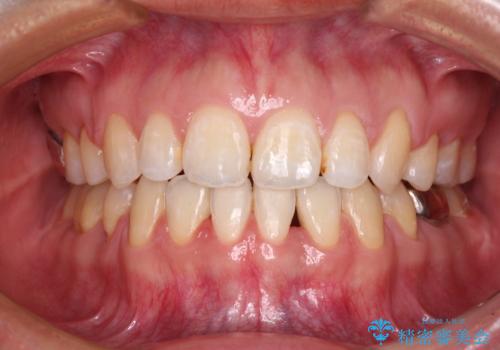

出っ歯を改善した後に真っ白な歯に 矯正歯科治療と審美歯科治療